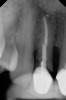

Fig 2. Radiograph showing implant was placed too deep and the diameter of the implant may be slightly larger than what was needed.

Figure 2

Caneva et al also suggested placing implants in a lingual (eg, cingulum) position to achieve optimal esthetic outcomes. The authors assessed the effect of implant positioning on resorptive patterns of the alveolar bone crest and demonstrated the importance of placing implants in a lingual position to minimize buccal bone resorption and thus prevent exposure of the implant. In their study, an average of 0.6 mm more buccal bone resorption was seen on implants that were placed in the center of the socket when healing after 4 months was compared histologically with implants that were positioned toward the lingual bony wall.17 In addition, placing a wider-diameter cylindrical implant in the extraction socket with the aim of filling the void between the implant and the inner socket wall was also shown to present greater buccal alveolar bone resorption (Figure 2).18,19 Based on these findings, it has been suggested that implant placement be performed in the palatal position of the socket to allow the formation of a gap between the implant surface and the inner buccal bone wall surface.19 More recently, in a retrospective cohort study, Cosyn and coworkers evaluated 115 patients who underwent implant placement with function. At 31 months, the buccal shoulder position of the implant was significantly associated with an increased likelihood of midfacial recession.3